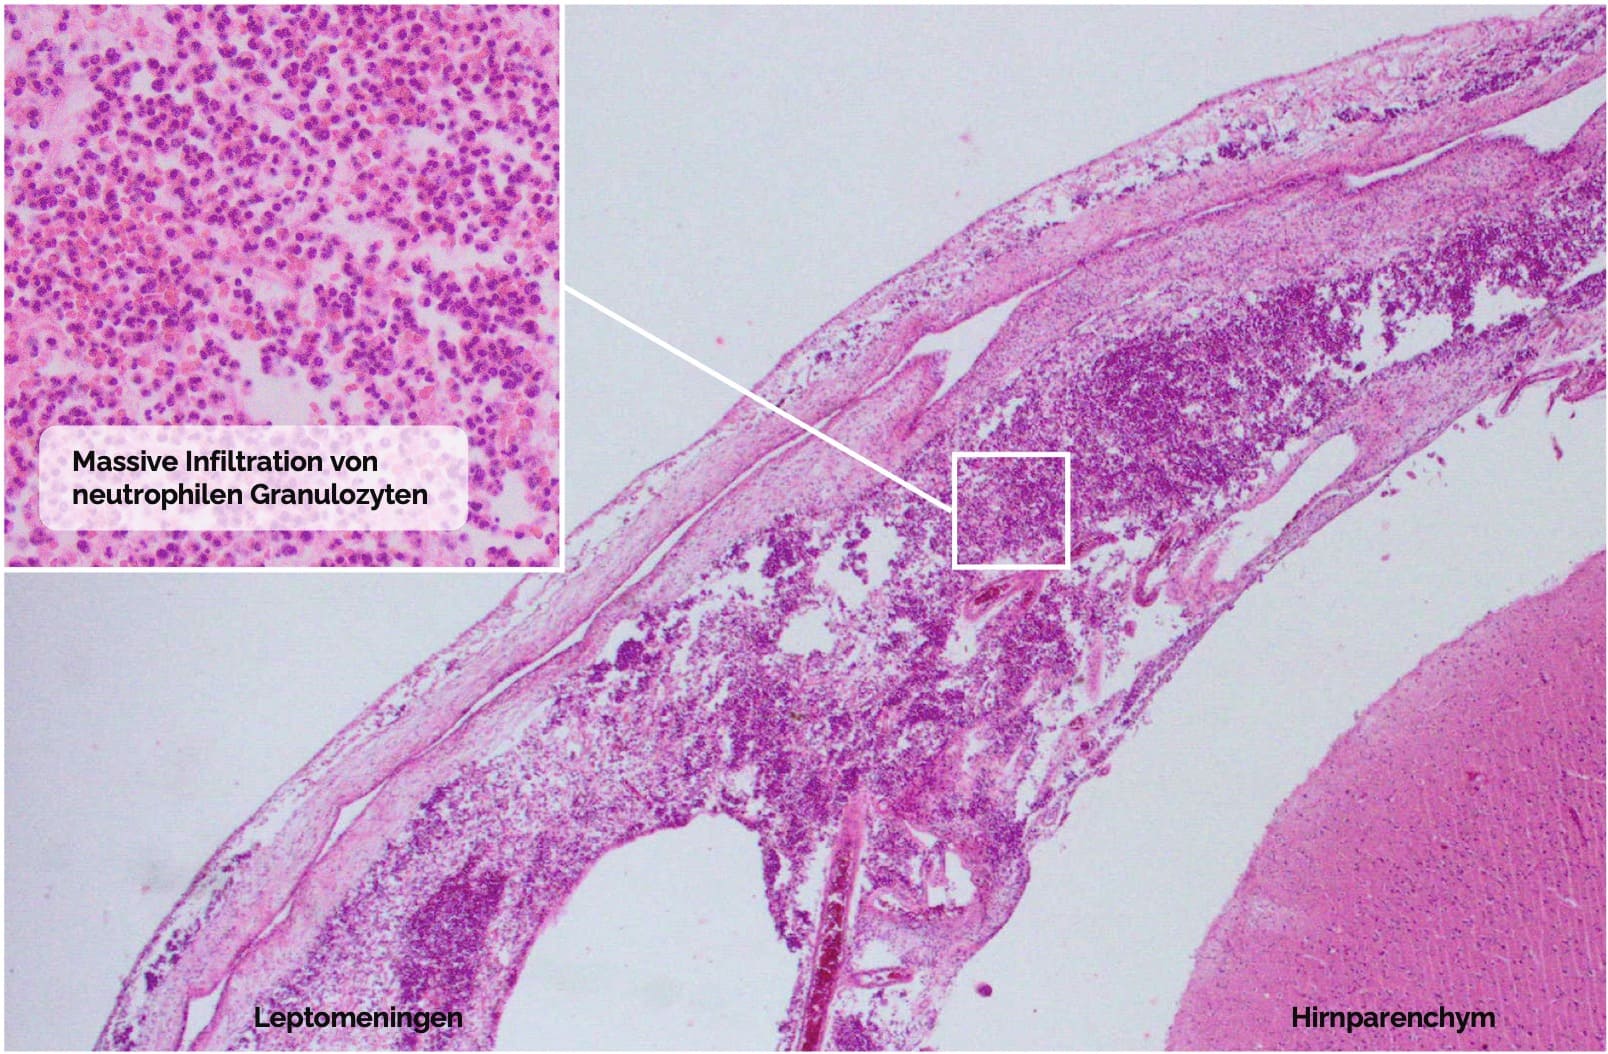

Bakterielle Meningitis

Eitrige (purulente) Form

Pathogenese: Eitrige Entzündung des Subarachnoidalraums mit ausgeprägter neutrophiler Granulozytenreaktion und proteinreichem, trübem Liquor

Mikroskopie:

Dichte Ansammlung neutrophiler Granulozyten im Subarachnoidalraum und als Infiltrat in den Leptomeningen

Mikroskopischer Befund der eitrigen Form einer bakterieller Meningitis